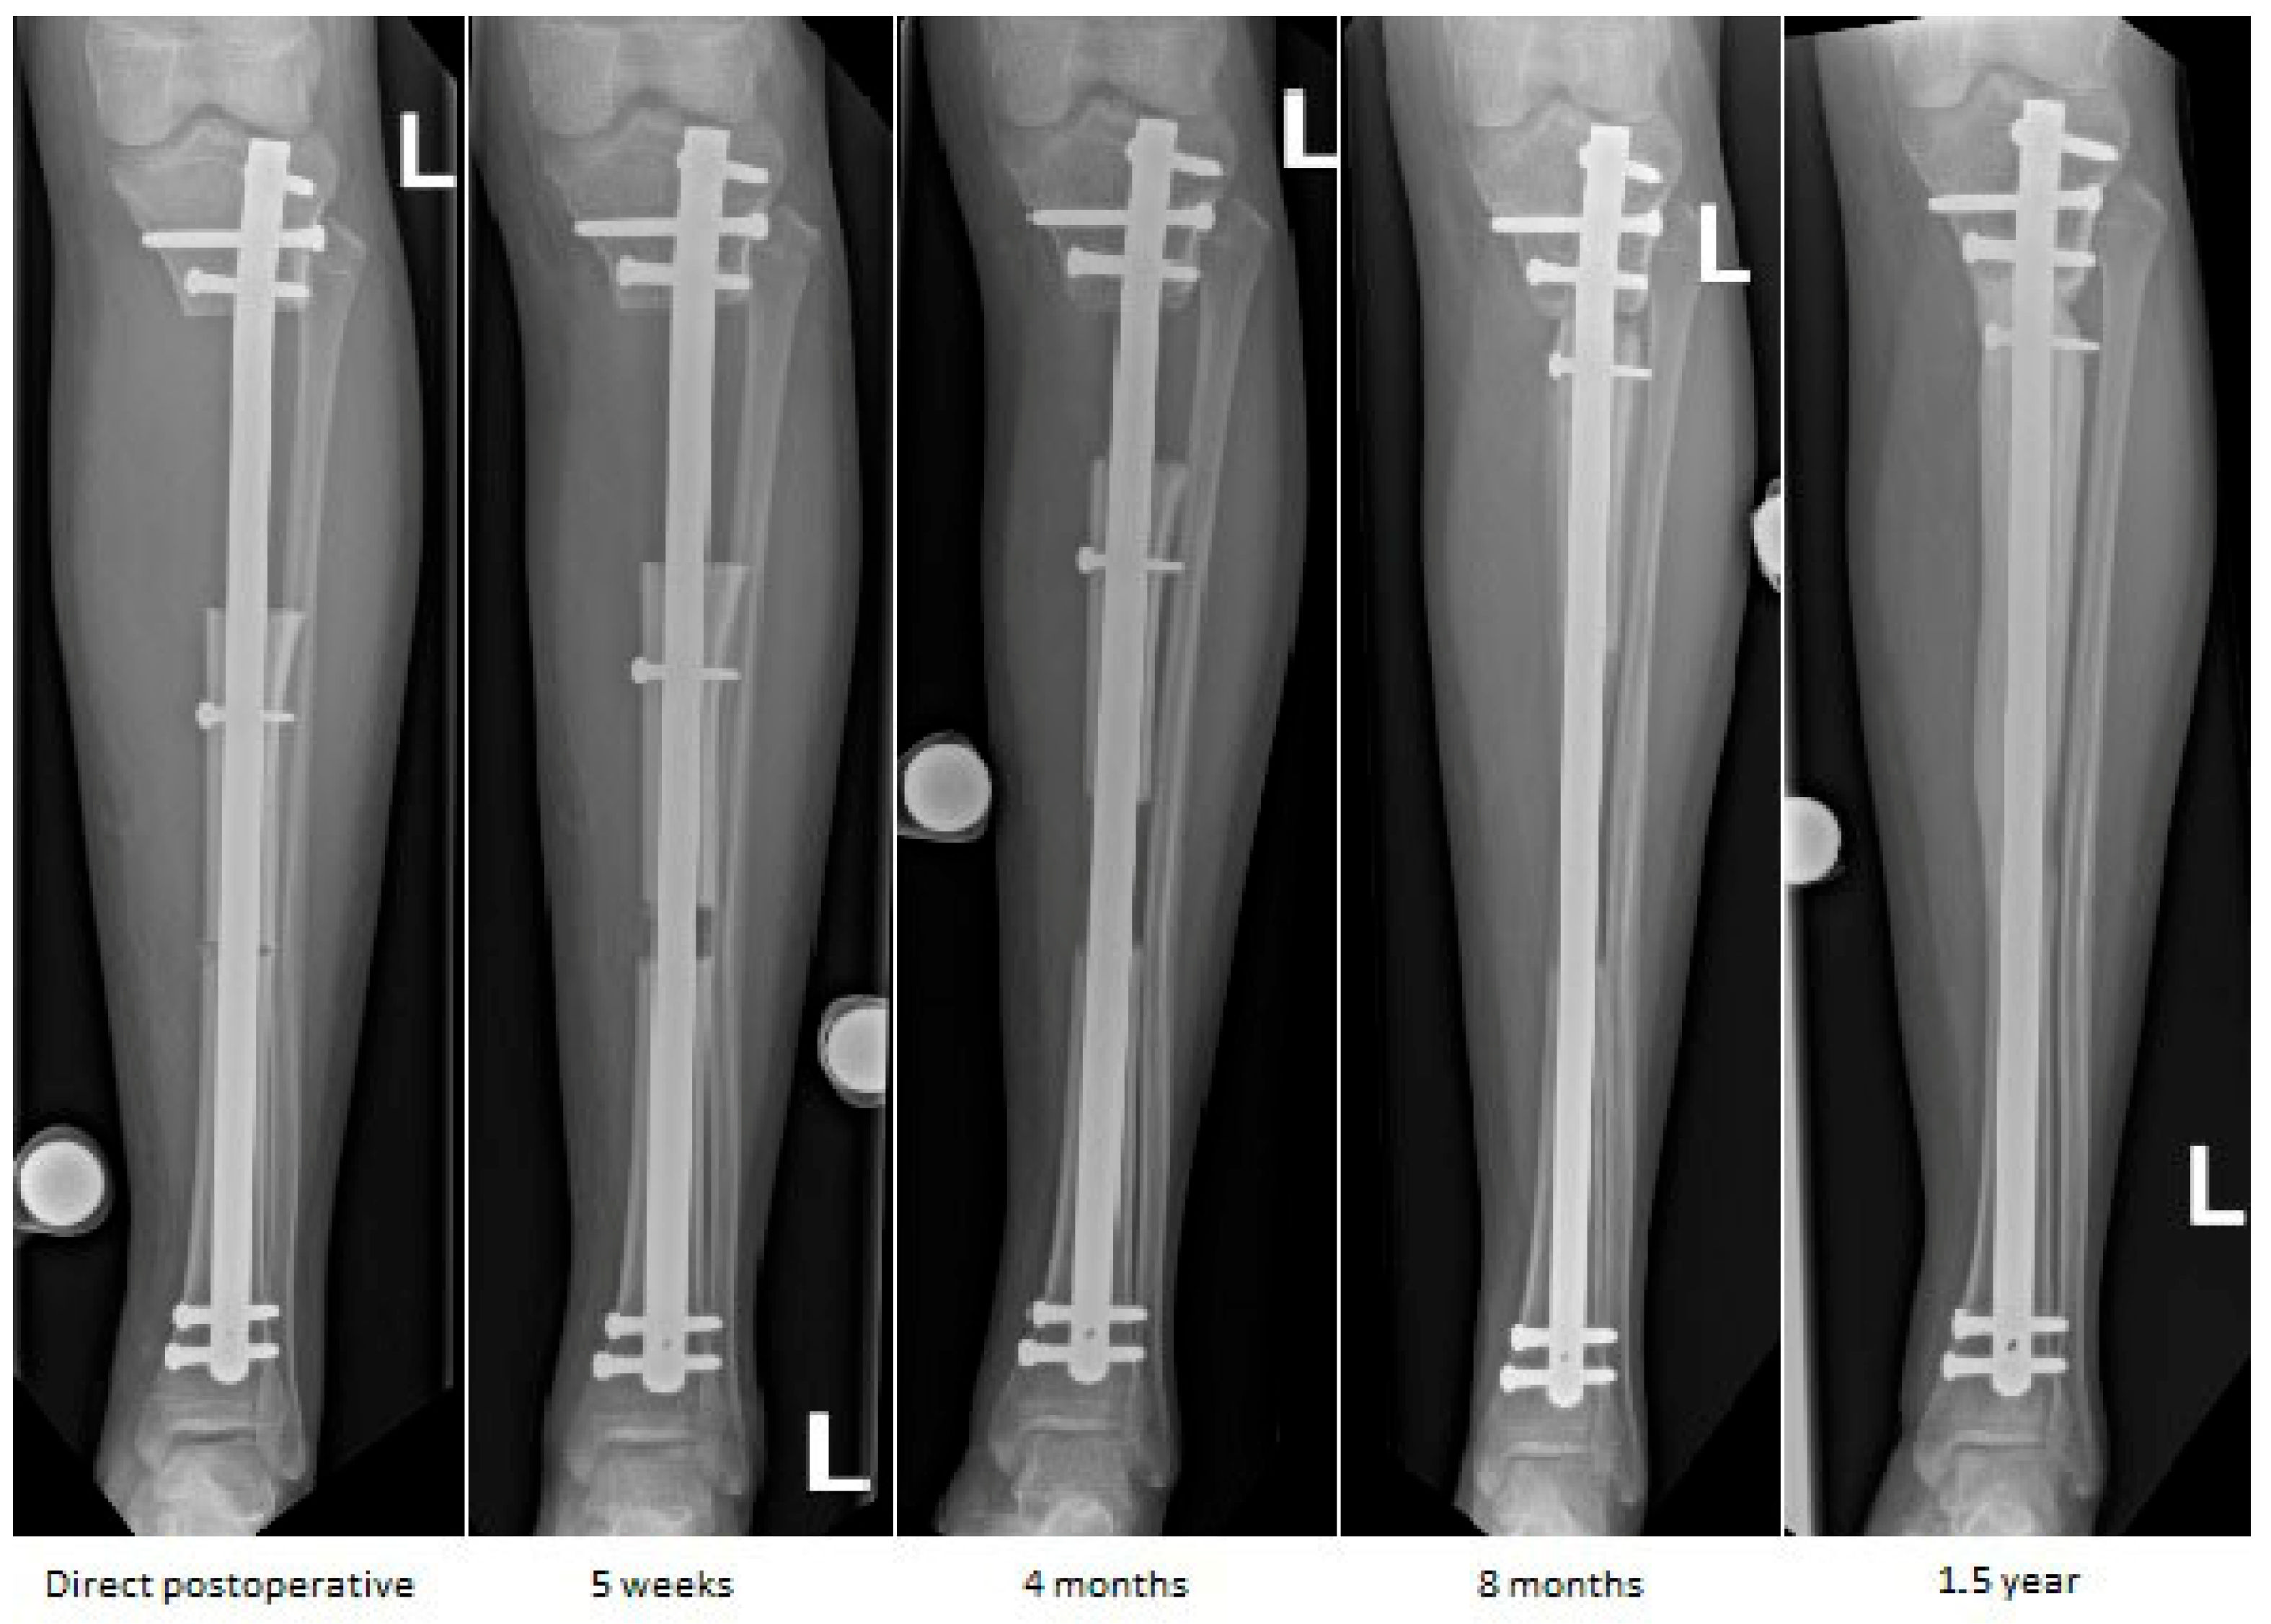

Figure 6.

Sequential anteroposterior radiographs following retrograde tibial bone transport at direct postoperative, 5 weeks, 4 months, 8 months, and 1.5 years. The initial segmental defect measured 9 cm. Remaining defect measured 8.5 cm at 5 weeks, 7 cm at 4 months, 1.5 cm at 8 months, and fully consolidated at 1.5 years. Progressive transport and callus formation are evident, with complete restoration of tibial length and alignment at 1.5 years. Distances are approximate due to image scaling.